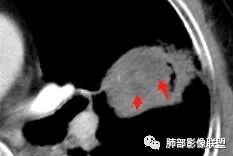

空洞内侧软组织肿块,比较支持恶性吧

这个空洞的性质很重要,对最后诊断结果影响大,如果中间没有曲菌球,那就是偏心空洞,指向恶性,如果是曲菌球引起的新月形改变,那就不一定。至于到底是曲菌球还是偏心空洞,需要仔细看看强化情况。

如果强化明确,那就可以排除曲菌球。

2、偏心空腔病灶,气腔略呈新月形,壁不规则,腔内结节相对密实,明显强化且不均,支持新生物而非曲菌球等。炎性空洞多有强化环。